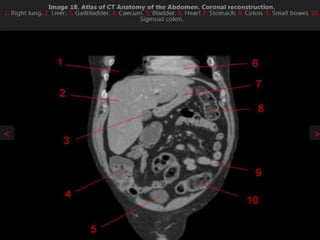

MRI anatomy images of the abdomen.

MRI anatomy imagesof the abdomen.